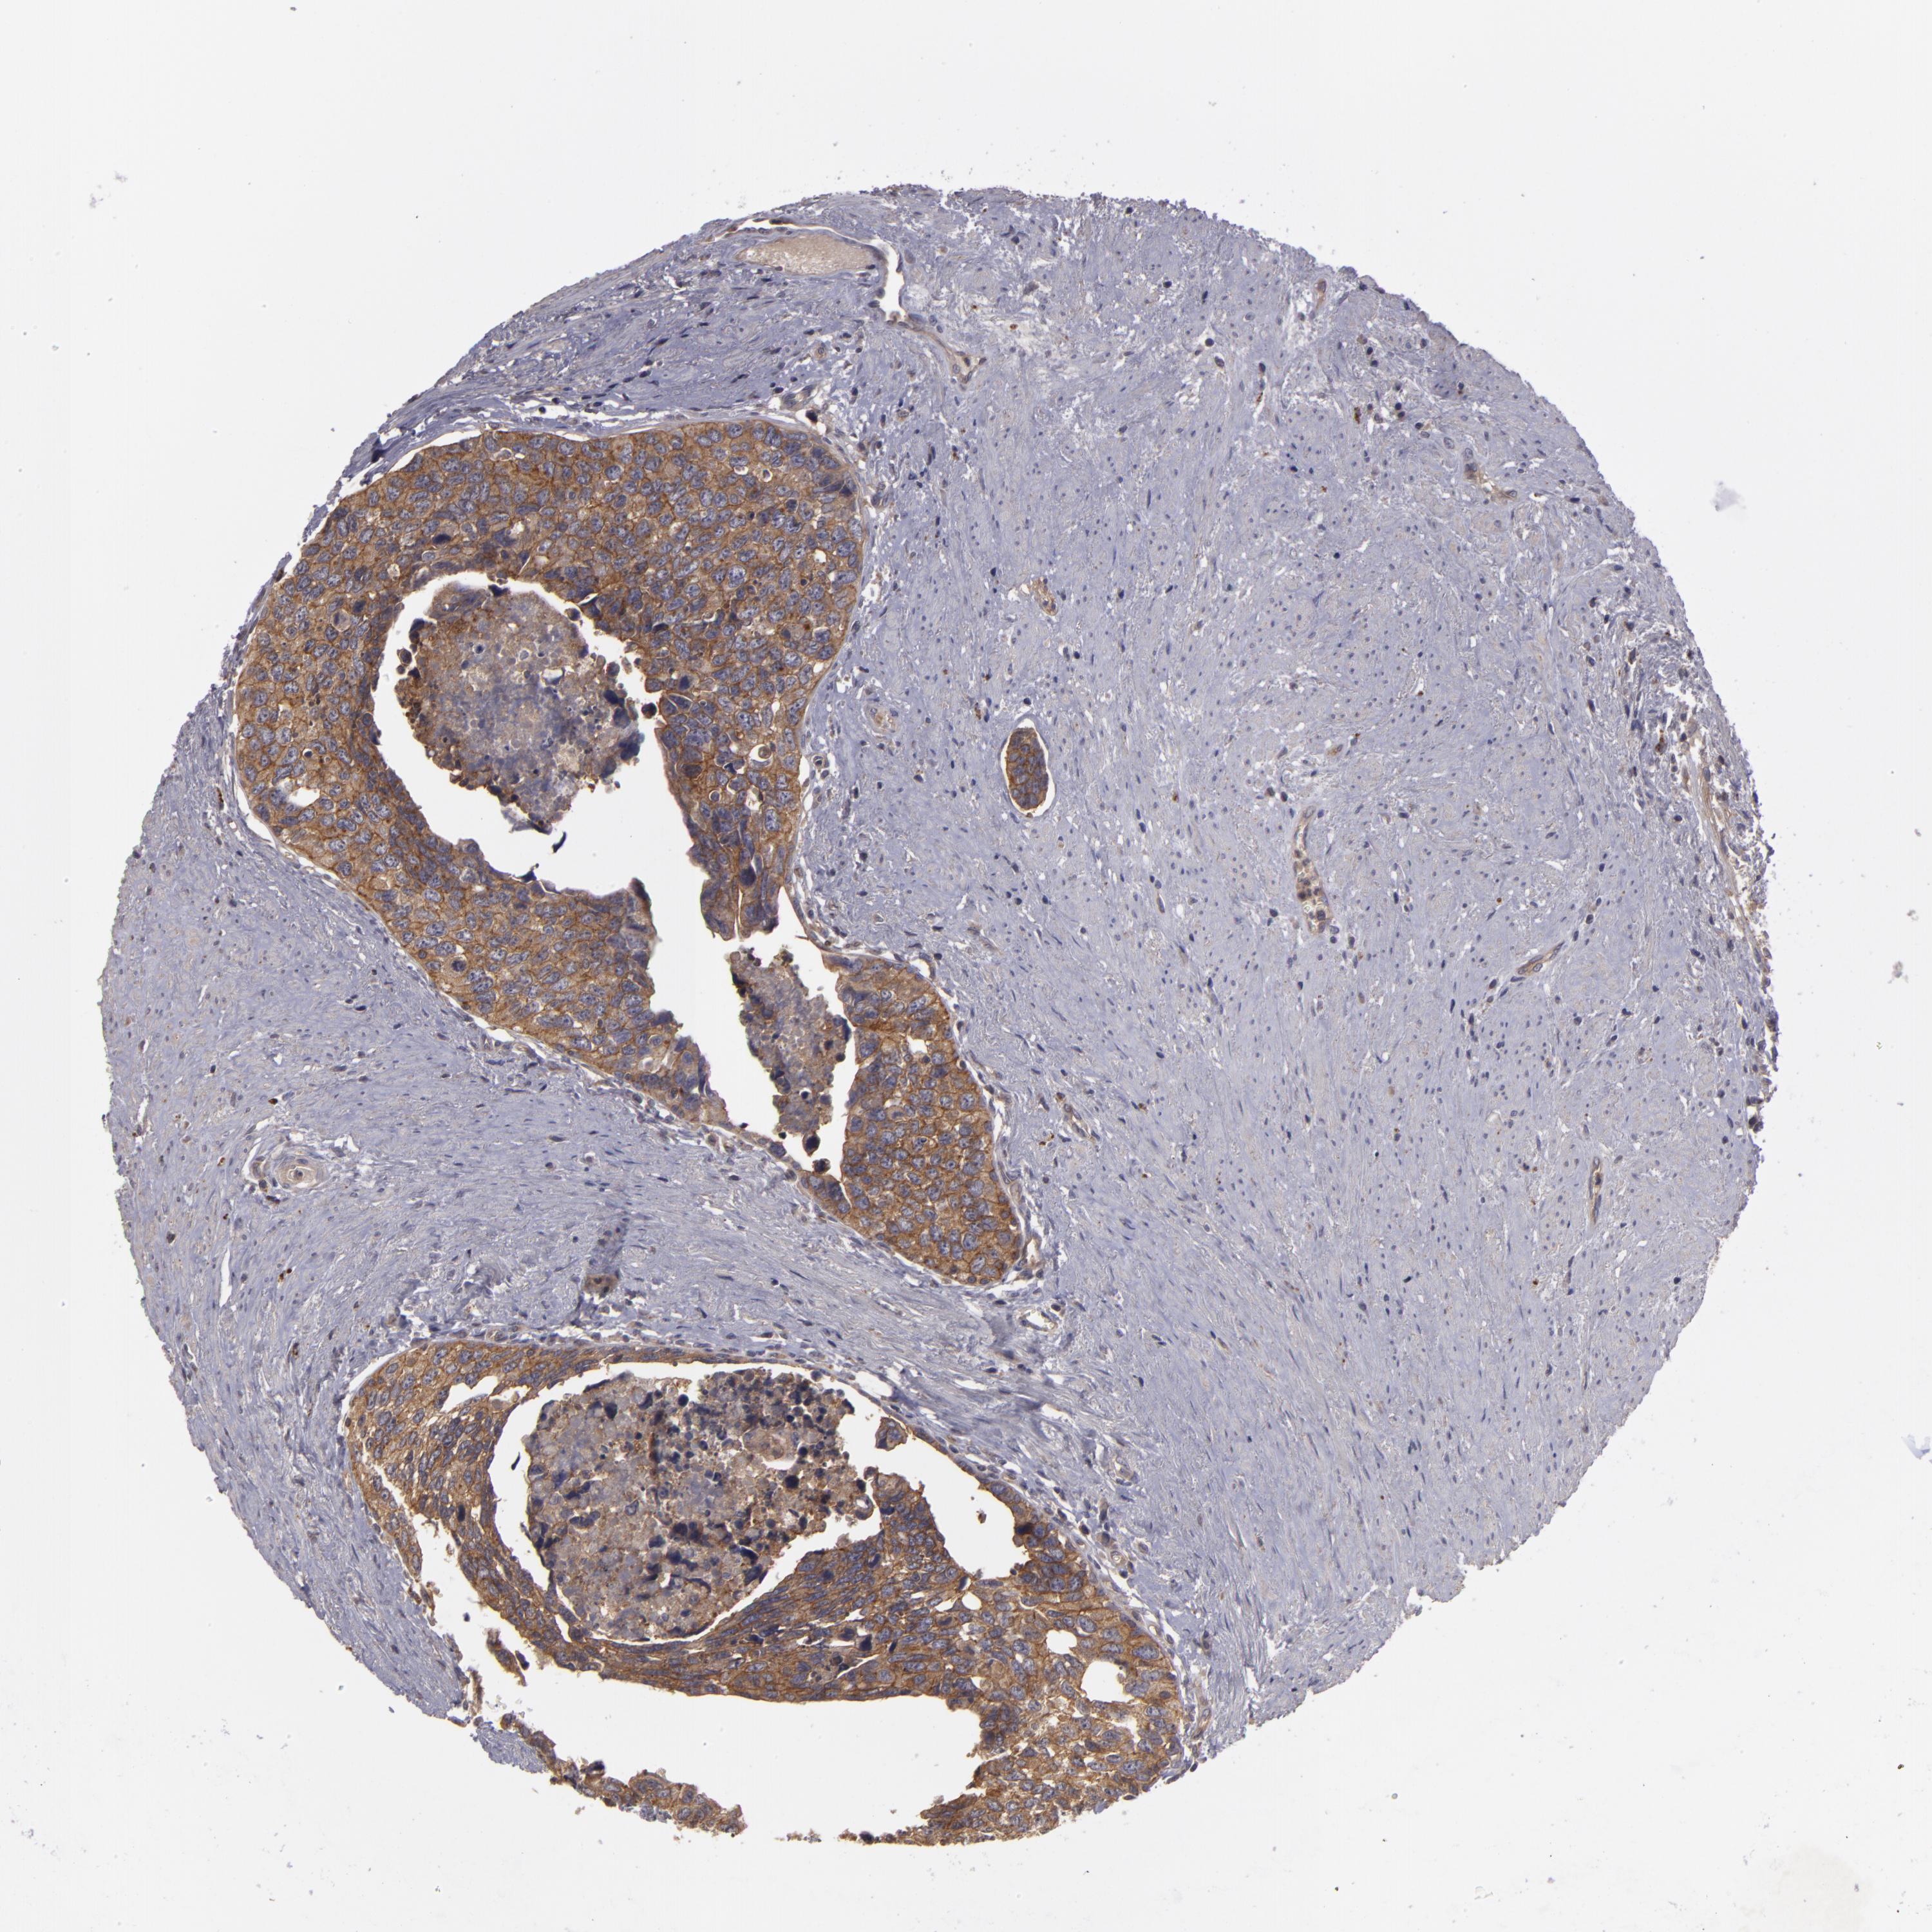

UROTHELIAL CANCER - Protein expressioni

A mouse-over function shows sample information and annotation data. Click on an image to view it in a full screen mode. Samples can be filtered based on level of antibody staining by selecting one or several of the following categories: high, medium, low and not detected. The assay and annotation is described here.

Note that samples used for immunohistochemistry by the Human Protein Atlas do not correspond to samples in the TCGA dataset.

Antibody stainingi

Antibody staining in the annotated cell types in the current human tissue is reported as not detected, low, medium, or high, based on conventional immunohistochemistry profiling in selected tissues. This score is based on the combination of the staining intensity and fraction of stained cells.

Each image is clickable and will lead to virtual microscopy that enables deeper exploration of all samples and also displays staining intensity scores, fraction scores and subcellular localization as well as patient and tissue information for each sample.

HPA049830

Urothelial carcinoma, High grade

Urothelial carcinoma, NOS

Urothelial carcinoma, Low grade

Adenocarcinoma, NOS